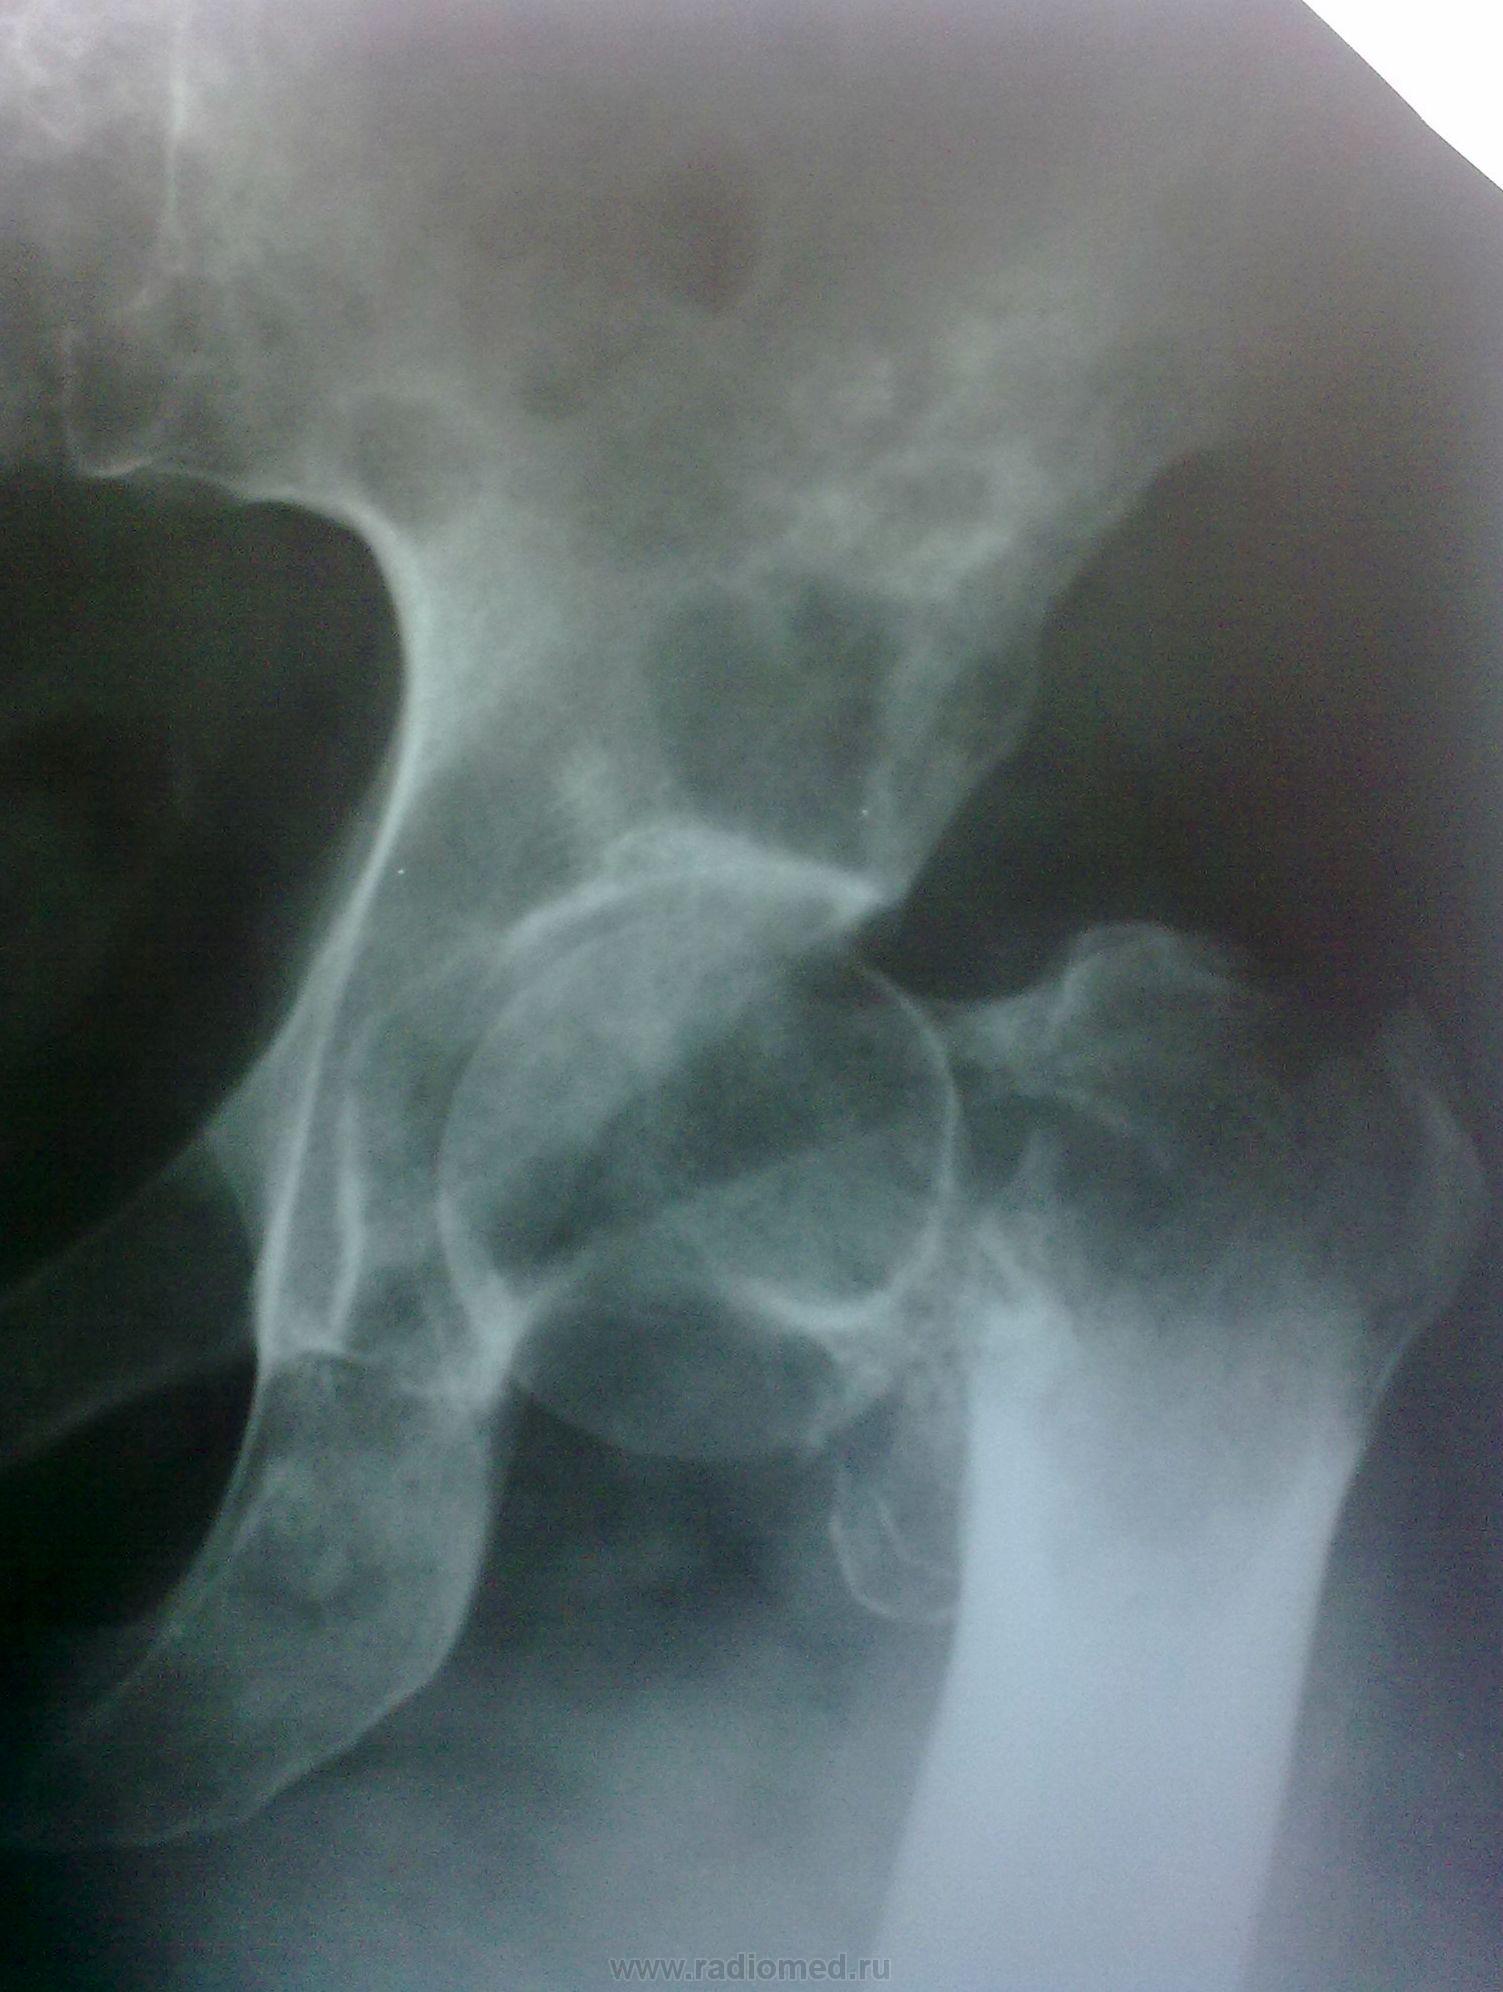

Пол пациента: Женский пол Тип патологии: Злокачественное новообразование Область исследования: Скелетно-мышечная система Методы исследования: Rg Рентгенограммы коллеги, врача-гинеколога, отказавшейся в свое время от мастэктомии по поводу злок. новообразования, лечившейся консервативными методами. https://radiomed.ru/sites/default/files/styles/case_slider_image/public/user/3055/samolechenie_raka_molochnoy_zhelezy_2.jpg?itok=h21nwmoF https://radiomed.ru/sites/default/files/styles/case_slider_image/public/user/3055/samolechenie_raka_molochnoy_zhelezy_3.jpg?itok=TTNqSoqp ID:9204 Вс, 21/11/2010 - 10:24 #1 Helios Не на сайте Был на сайте: 7 месяцев 2 недели назад Зарегистрирован: 06.08.2010 - 15:16 Публикации: 4417 No comments. Вс, 21/11/2010 - 15:09 #2 lupan Не на сайте Был на сайте: 6 лет 10 месяцев назад Зарегистрирован: 07.01.2010 - 17:17 Публикации: 1406 Что же. Сапожник без сапог. Великое преймущество врача заключается в том, что он не обязан следовать собственным советам. ( А. Кристи) Вс, 21/11/2010 - 20:21 #3 Катенёв Валенти... Не на сайте Был на сайте: 7 лет 1 неделя назад Зарегистрирован: 22.03.2008 - 22:15 Публикации: 54876 Обработанные снимки.Приложения: Пнд, 22/11/2010 - 20:18 #4 tatyana Не на сайте Был на сайте: 4 года 1 месяц назад Зарегистрирован: 24.06.2009 - 08:33 Публикации: 2090 Игорь иванович, а почему Вы так назвали тему? Вы считаете, что мастэктомия гарантирует от мтс в кости? Это не так. "самоуверенность дилетантов - предмет зависти профессионалов" Пнд, 22/11/2010 - 21:36 #5 Игорь Иванович Не на сайте Был на сайте: 3 года 9 месяцев назад Зарегистрирован: 23.01.2010 - 14:56 Публикации: 3695 tatyana wrote: Игорь иванович, а почему Вы так назвали тему? Вы считаете, что мастэктомия гарантирует от мтс в кости? Это не так. Да нет, я так не считаю, слишком много видел. А назвал, потому что доктор!!! Ауто знала, ауто отказалась от операции. Пнд, 22/11/2010 - 22:33 #6 tatyana Не на сайте Был на сайте: 4 года 1 месяц назад Зарегистрирован: 24.06.2009 - 08:33 Публикации: 2090 Почему же тогда - беспечность? может наоборот - информированность? "самоуверенность дилетантов - предмет зависти профессионалов"

Обработанные снимки.